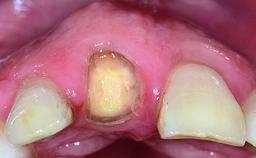

Replacement of a Failing Upper Left Central Incisor: Immediate Placement of an RC Bone Level Implant and Provisionalization

A healthy 23-year-old female patient was referred for a consultation on replacing tooth 21 with an implant-supported restoration. The patient had recently moved to the area and reported a history of endodontic and periodontal treatment for tooth 21. The tooth had been deemed non-restorable by her previous periodontist but since she was going to be moving, he recommended consulting to a dentist in her new city to continue her treatment. A review of her medical history yielded no significant findings and no known drug allergies. The analysis of her smile revealed a medium to high symmetrical smile line and a slightly discolored tooth 21.

Provisional Implant-Supported Prosthesis Prosthodontic margin < 3 mm apical to mucosal margin Prosthodontic margin < 3 mm apical to mucosal margin

Soft Tissue Contour and Volume Ideal